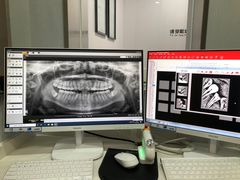

• -牙博士口腔品牌连锁(杨浦店)

Julia511 | 21-01-30

报错